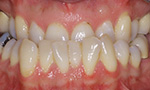

Zahn- und Kieferfehlstellungen

Zahn- und Kieferfehlstellungen können genetisch bedingt sein, sie können aber auch im Laufe der Jahre, z.B. durch Fehlfunktionen, entstehen oder als Kombination von beidem auftreten. Bei einer korrekten Zahnstellung und Kieferlage passen Ober- und Unterkiefer in allen drei Raumebenen perfekt zusammen.

Die häufigsten Fehlstellungen

Nach Prüfung der Funktionen des Gebisses, wie zum Beispiel des Ineinanderpassens der Zahnreihen oder der Funktion des Kiefergelenks, steht fest, welche der folgenden Fehlstellungen vorliegt: